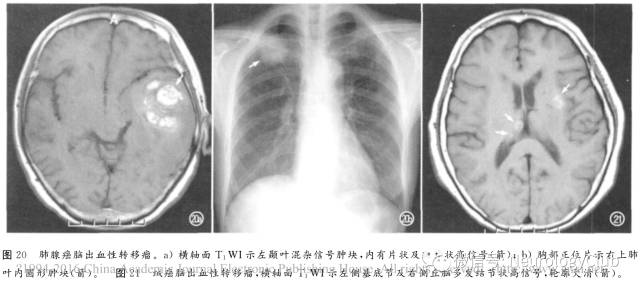

2. 转移瘤

转移性肿瘤如支气管肺癌(图20)、肾细胞癌、黑色素瘤、绒癌(图21)、甲状腺癌最易出血,且常为多发性,短T1成分表示亚急性期及慢性早期出血。主要与海绵状血管瘤及其它隐匿性血管畸形相鉴别。增强扫描时非出血部分强化以及脑外肿瘤史有助于诊断。